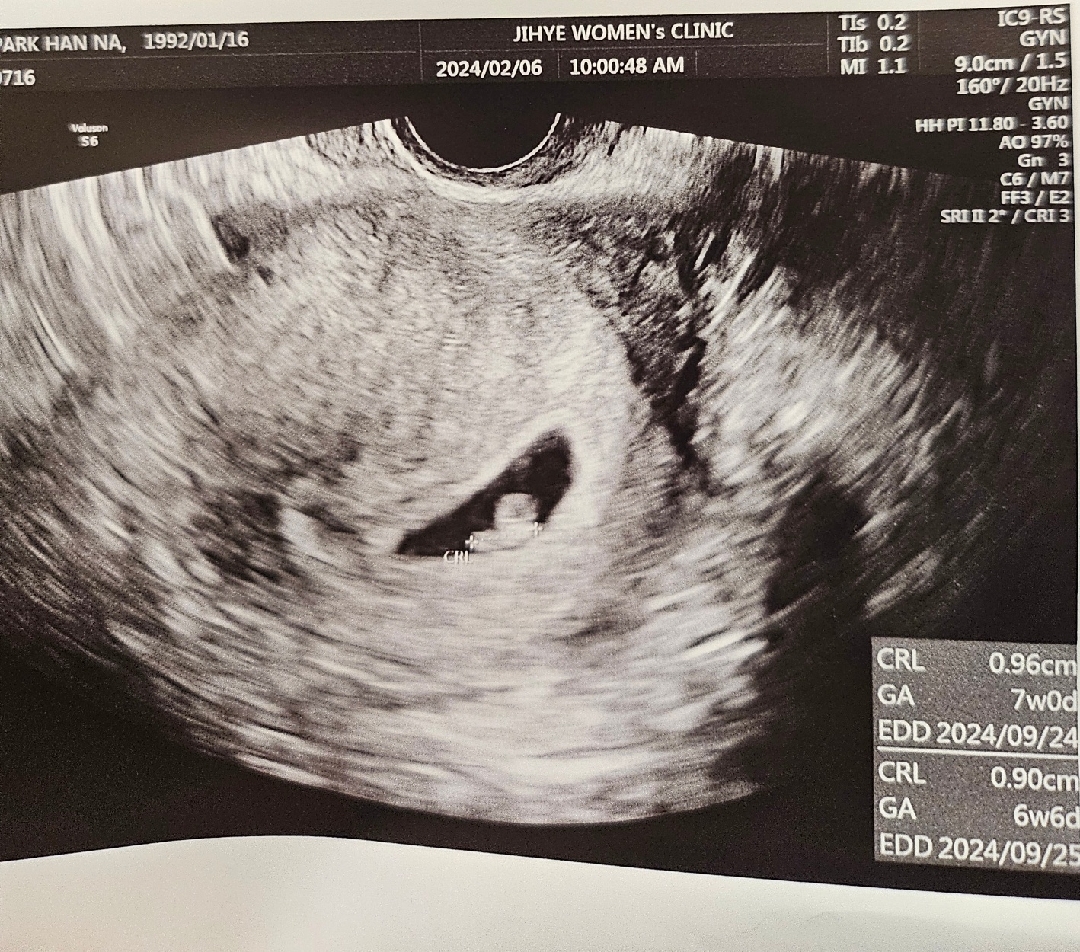

다른분들은 예쁜다이아반지같던데 저는 왜케 달팽이같죠.. 난황도 링모양도 아니구... 정상적으로 크고있는거맞겠죠ㅜㅜ?

다이아반지 모양 보시려면 6주 초중반에 가셔야할거예요ㅜ 아기들이 한주 한주 쑥쑥 크더라구요~ 동그란 모양에서 그사이에 쑥 커서 벌써 1센치가 다되어가니 너무 대견한거 같은데요~ 넘나 귀여워요💕

저도 심소들을때 모양 비슷했어요 ㅎㅎ 저러고 7주차에 2등신도 읭? 스러운데 나중에 잘커서 8주 아주 귀엽고 완벽한 젤리곰도 봤으니 걱정마세요!!